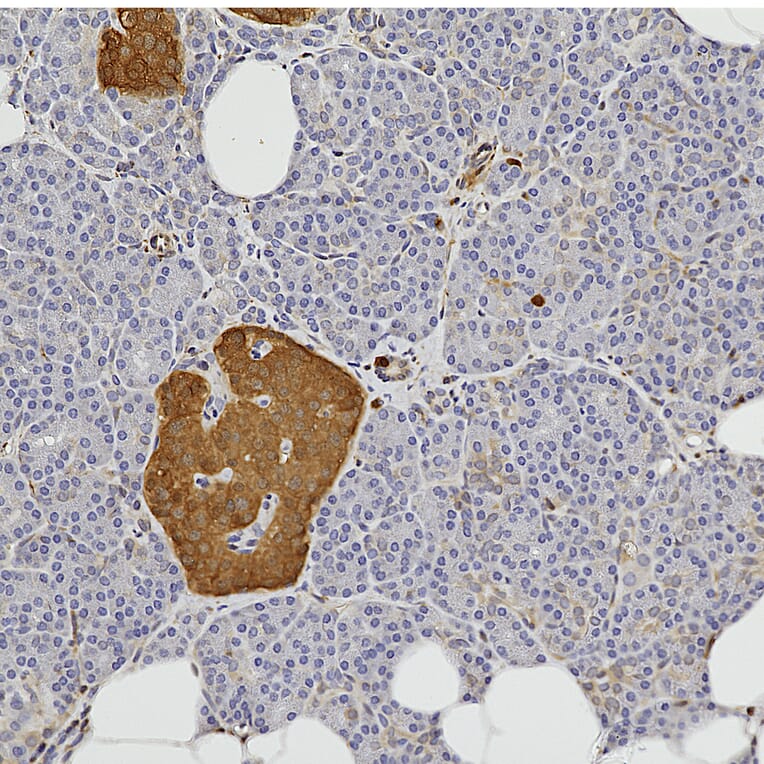

Immunohistochemistry analysis of a formalin fixed paraffin embedded human pancreas section with Anti-NSE Antibody (A104334) at a dilution of 1:10,000 detected in DAB (brown) following the ABC method. Counterstained with Hematoxylin (blue). The NSE antibody robustly stains the neuroendocrine cells of pancreatic islets.